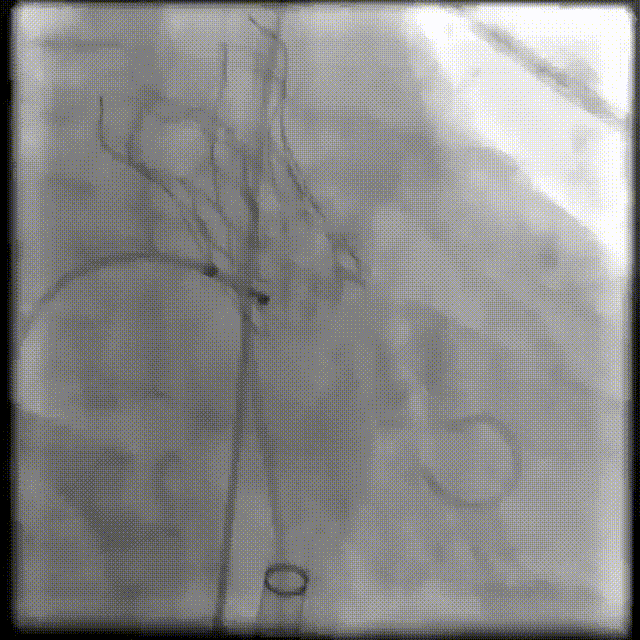

输送系统定位

瓣膜释放

珠海市人民医院超声科张恒教授术中使用食道超声评估瓣膜形态、瓣膜植入深度、反流及瓣周漏情况